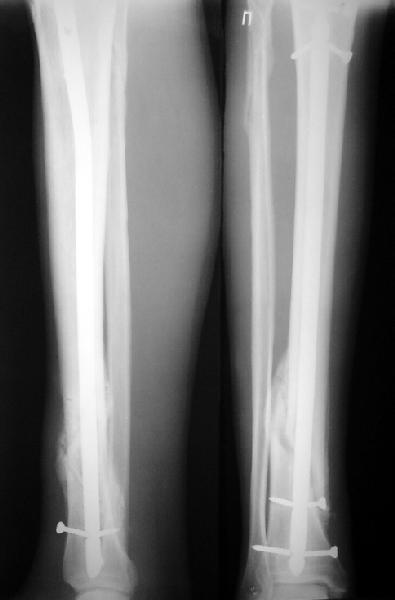

По крайней мере ходящих без дополнительной опоры через 1 месяц после операции с небольшой - при изолированной травме немало. Нестабильные по оси, кстати, не только оскольчатые, но и спиральные.

И если пациент еще не возвращается к полной нагрузке и функции, то не потому, что не разрешает врач, опасаясь несостоятельности фиксации.

Как мне показать пример? Фото стоящего на одной оперированной конечности пациента? O! Пример, подвигнувший нас на некоторое изменение технологий. Пациент этот ходил с полной нагрузкой вопреки рекомендациям. В качестве подтверждения - сломанный проксимальный статический винт к 1 мес., а к 2 мес. - все остальные. Сейчас мы перешли на более fool-proof остесинтез.